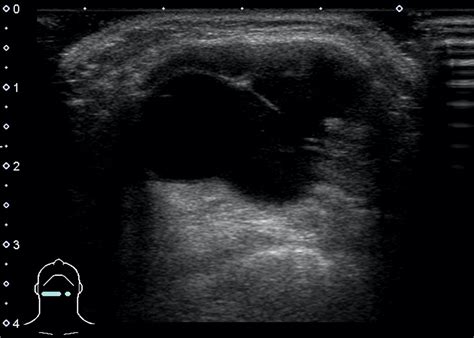

The diagnosis of a Cyst Thyroglossal Duct typically involves a combination of physical examination and imaging studies. The healthcare provider will perform a thorough physical examination to assess the size, location, and characteristics of the cyst. Imaging studies, such as ultrasound, computed tomography (CT) scan, or magnetic resonance imaging (MRI), may be ordered to confirm the diagnosis and rule out other potential causes of the neck mass.